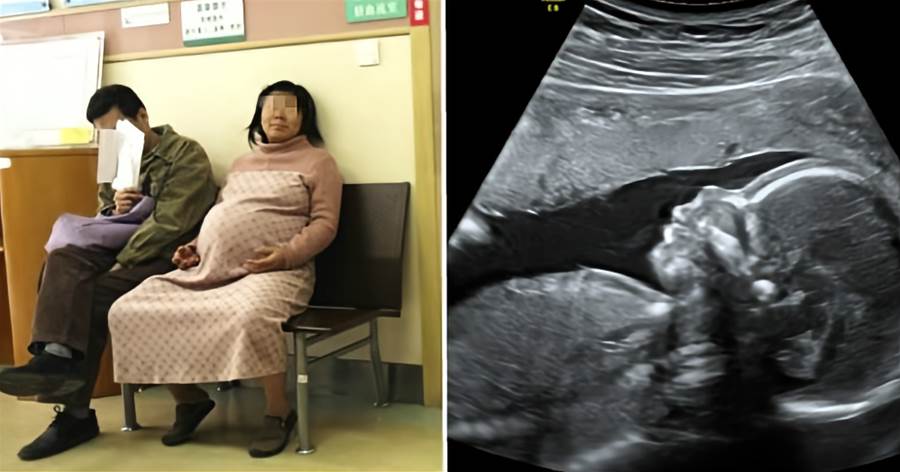

台灣有許多人都會去算命,但算命說的話當個參考就好,可別過度迷信,有一位孕婦寶寶就要出生了,但她卻說時辰未到,寶寶太早出生會歹命,決定要拖到2天後才要生,甚至羊水都流乾了,還跑去北投找算命仙,算命仙也說好的時辰還沒到,讓醫護整個超級傻眼!

根據《ETtoday新聞雲》報導,有一名婦產科醫生在電視上分享遇到一位超扯的迷信孕婦,其實她早就已經要生了,但是她卻硬撐不讓寶寶出來,還說「我寶寶本來是3號,已經算好是公主命,我不要現在生!」,但是寶寶與孕婦狀況已經越來越差,醫護本來想直接強制她上產房,卻發生拉扯,孕婦羊水都流乾了還衝去北投找算命仙,完全不顧孩子的狀況。

當時醫生已經發現寶寶心跳不太穩定,孕婦體溫也越來越高,那時已經下午1點,拖延了12個小時,但孕婦卻寧願跟丈夫開車去找一位在北投深山的算命仙,也不相信醫生的專業,最後她回到醫院時是下午4點,還堅持說「算命仙說要酉時出生,因為女寶寶要下午6點多,才會是人緣好、有貴人運。」,醫護一直勸說這樣下去孩子會出事,但孕婦還是不肯生甚至哭給醫生看,最後歷經了17個小時終于推進產房,醫生也迅速把小孩拉出來,但孕婦驚喊「怎麼才6點13分,不行!我16分才能算生完」,硬讓自己多待了3分鐘,才讓醫生做後續處理,讓全場傻眼。

但是孩子出生後,也因為身體狀況不好,直接住進保溫箱裡面,醫生則無奈的說「其實這些都是不必要的,最好依正常狀況,什麼時候生就什麼時候生」,不少網友看完也傻眼表示「孩子有你這種迷信媽媽,才是真正的歹命」、「太誇張了吧,孩子本來可以健康出生的」、「迷信到沒辦法辨認是非對錯」、「算命仙又不是醫生,很多都是騙人的」引多討論。